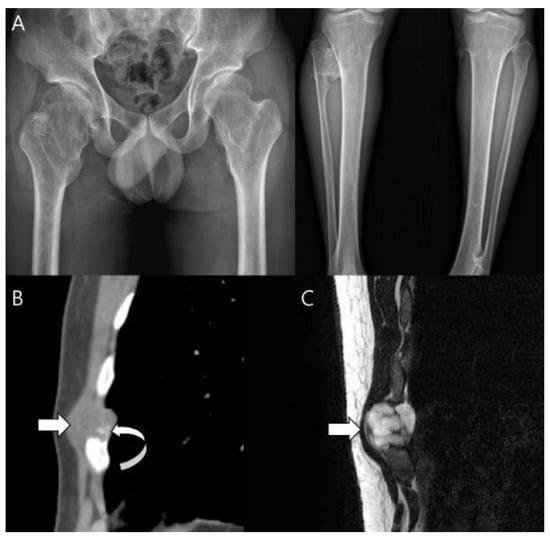

3.1. Distinction between Enchondroma and ACT

3.2. Biopsy or Follow-Up? Questions for Incidental Cartilage Lesions in the Long Bones